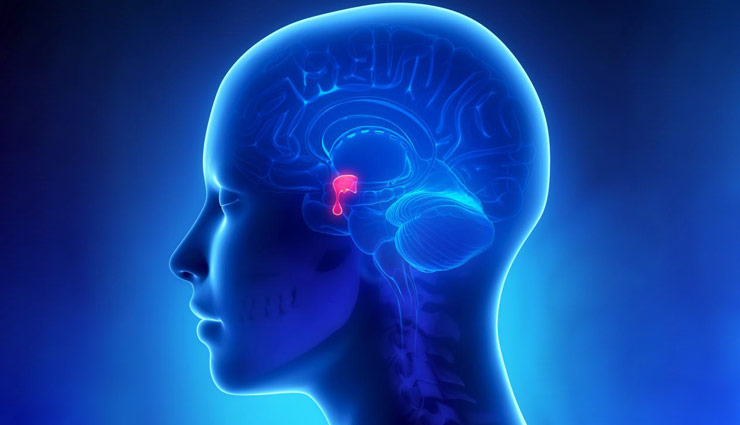

غده هیپوفیز کوچک و شبیه بیضی است و زیر دماغ در قسمت درونی مغز قرار گرفته است. غده هیپوفیز و هیپوتالاموس با ساختاری ساقهمانند به هم متصل هستند. هیپوتالاموس، بخش کوچکی از مغز است و در ایجاد تعادل میان عملکردهای مختلف بدن نقش دارد. هیپوتالاموس میزان ترشح هورمونها از هیپوفیز را هم کنترل میکند. غده هیپوفیز به ۲ بخش لوب پسین و پیشین تقسیم میشود.